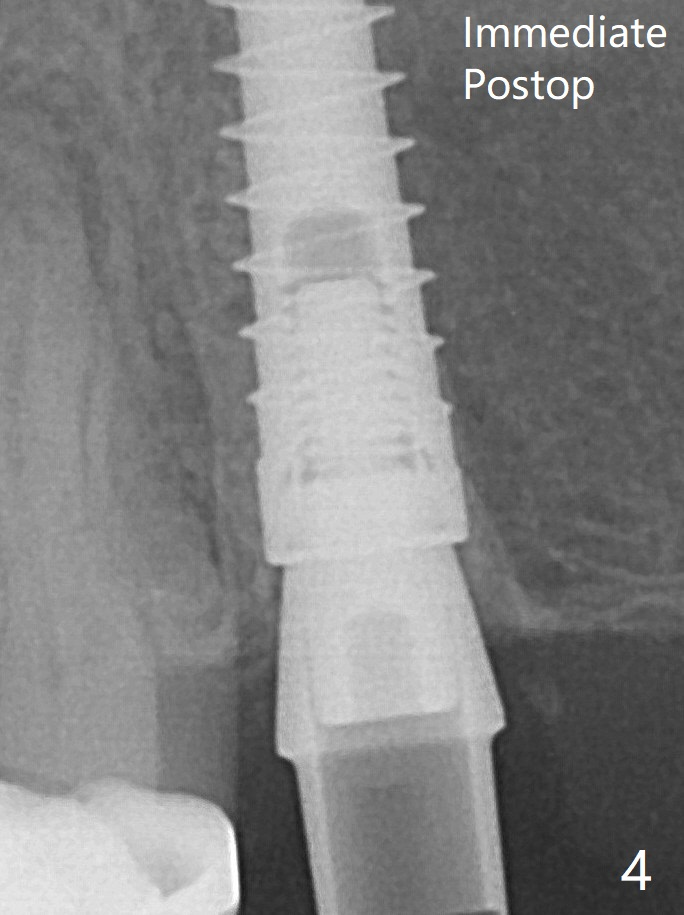

A relatively large 2-piece implant (3.5x13 mm) is placed (Fig.3), but a 4x5.7(2) mm abutment is incompletely seated (<).  Use of 4.6 and 5.6 mm bone profile drills does not appear to solve the problem.  The implant is backed up to the supra-gingival level so that it seems easier physically to insert the same abutment into the implant securely.  Then both of them are torqued into the place together (Fig.4).    The bone graft remains in place 4 months postop (Fig.6).